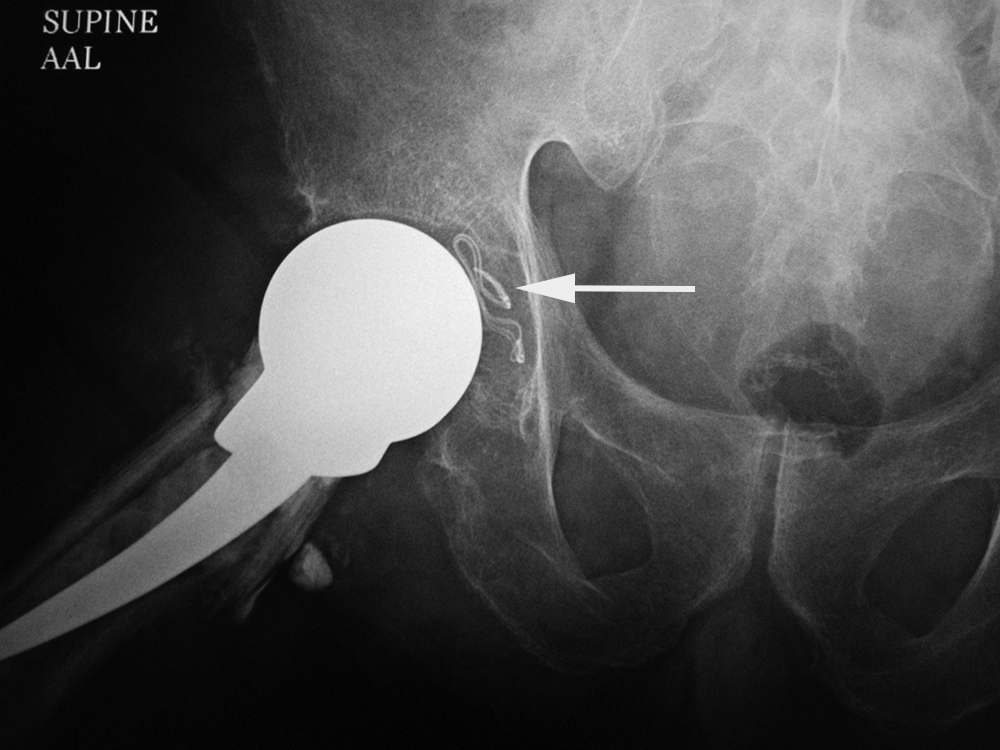

Acupuncture needles in the paraspinal subcutaneous soft tissues of 37 year-old Korean woman. The needle fragments were purposefully left in place. (Courtesy Dr. Joseph A. Alvarado). From Hunter, 1994 Elderly man with right hip pain and a draining sinus tract near the right hip. He had a right hip unipolar prosthesis placed several weeks prior in Mexico. Radiographs of the pelvis and right hip (left) show a unipolar prosthesis as well as a retained surgical sponge (arrow) in the medial aspect of the right acetabulum. The prosthesis was removed and replaced with a temporary antibiotic impregnated right hip "prosthesis" (right) made from antibiotic laden cement and held in place by press fitting and cerclage wires. Surgical sponges used at University Medical Center, Tucson, AZ. See Hunter, 2010.